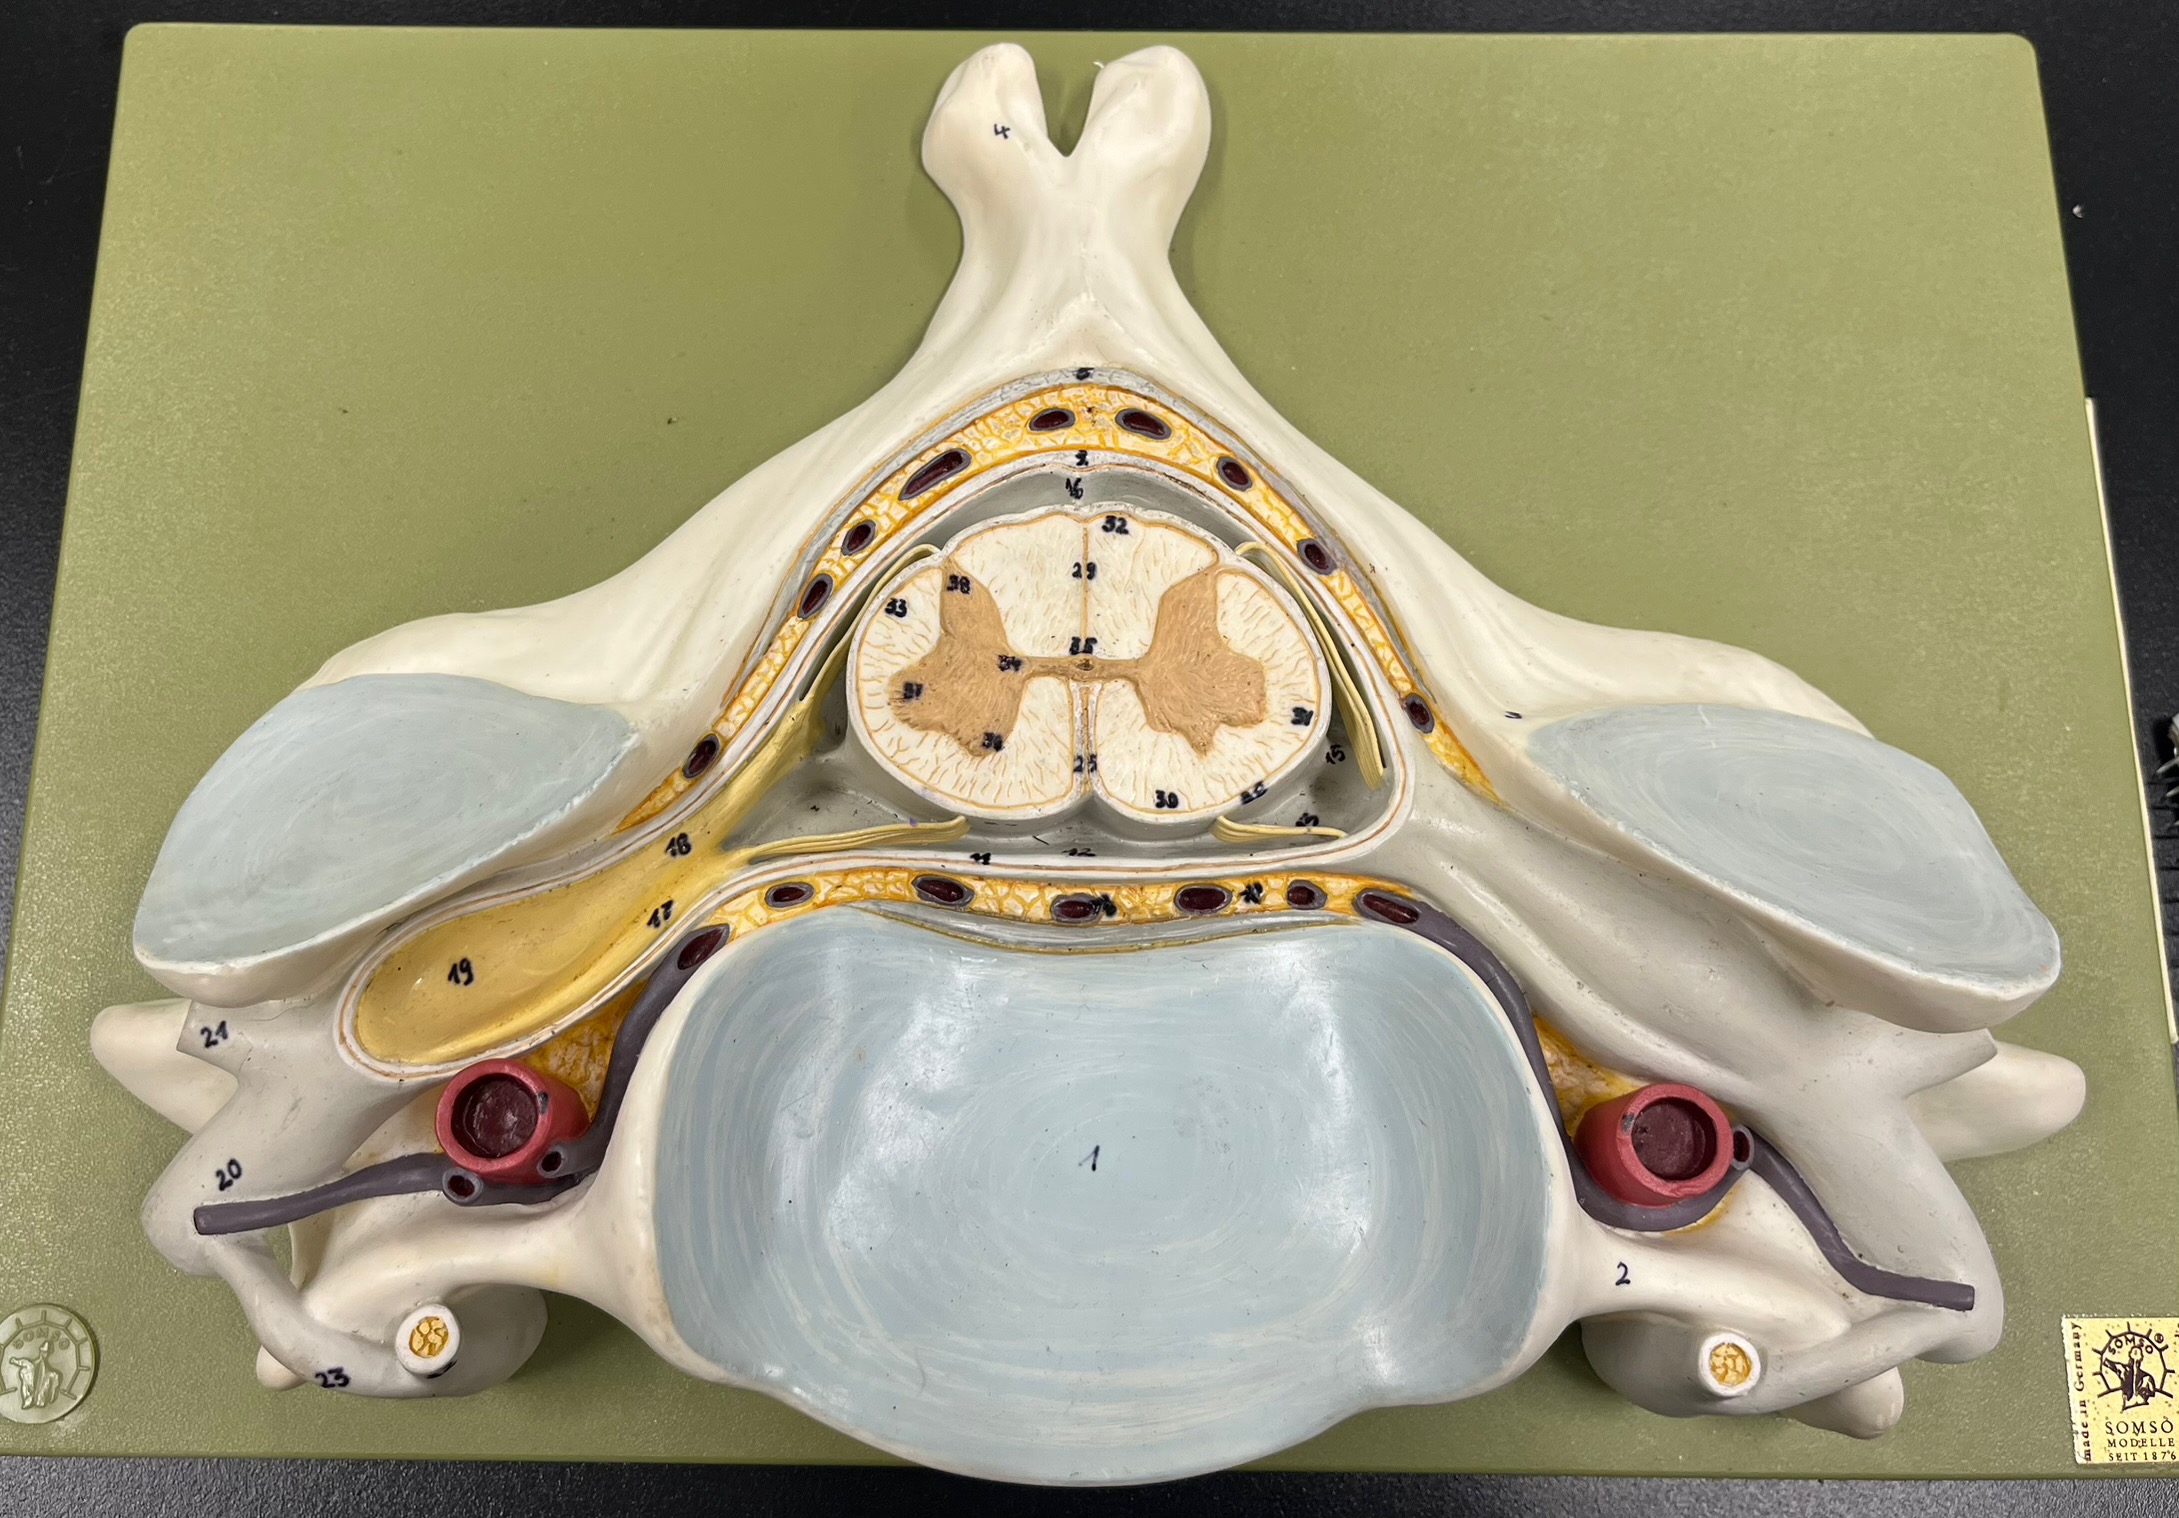

epidural space

dura mater

subdural space

arachnoid mater

subarachnoid space

pia mater

denticulate ligaments

What is the groove here?

anterior median fissure

posterior median sulcus

posterior (dorsal) horn

anterior (ventral) horn

lateral horn (selected models)

gray commissure

central canal

anterior column

lateral column

posterior column

white commissure

posterior (dorsal) root ganglion

What is the bulb here?

posterior (dorsal) root ganglion

posterior (dorsal) root

posterior (dorsal) root

anterior (ventral) root

anterior (ventral) root

dorsal ramus

dorsal ramus

ventral ramus

ventral ramus

rami communicantes

rami communicantes

sympathetic chain ganglia

sympathetic chain ganglia